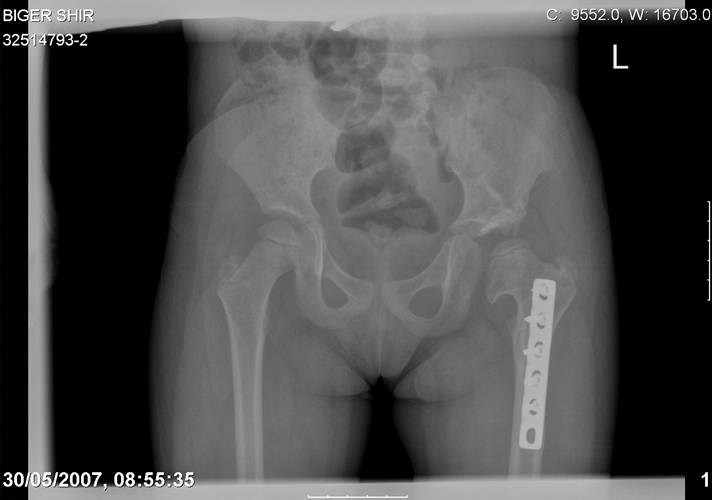

[Ortho] Врожденный вывих бедра

Navernoe Dega

Chto by ne byt goloslovnym posilau vam svoi sluchai gde sdelal vse chto napisal vyshe

Mark Eidelman